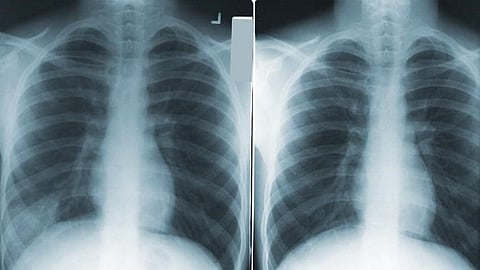

Lung cancer is one of the most common and serious types of cancer. Your odds of survival depend on when the cancer is diagnosed. It’s crucial to catch lung cancer at an early stage - that’s why getting screened is extremely important.